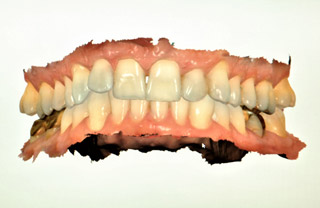

DIGITAL INTRAORAL SCANNER

Scanner can capture the true representation of your dentition in a digital format as opposed to the conventional manual impression technique. This digitally captured image can be used in variety of way. The images can be used to fabricate crowns, bridges, partial dentures, bruxing appliances and more. Using digital workflow allows for an additional tool to improving patient care.